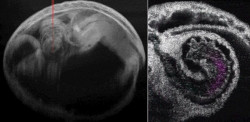

Desarrollan en el laboratorio un organoide que reproduce un corazón embrionario

Hubo un tiempo en que la idea de desarrollar órganos en el laboratorio era materia de ciencia ficción. Hoy en día, la biología de células madre y la ingeniería de tejidos están convirtiendo la ficción en realidad con la llegada de los organoides: pequeños tejidos y órganos cultivados en laboratorio que son anatómicamente correctos y fisiológicamente funcionales que en un futuro podrían proporcionar una producción bajo demanda de tejidos y mini órganos para la investigación.